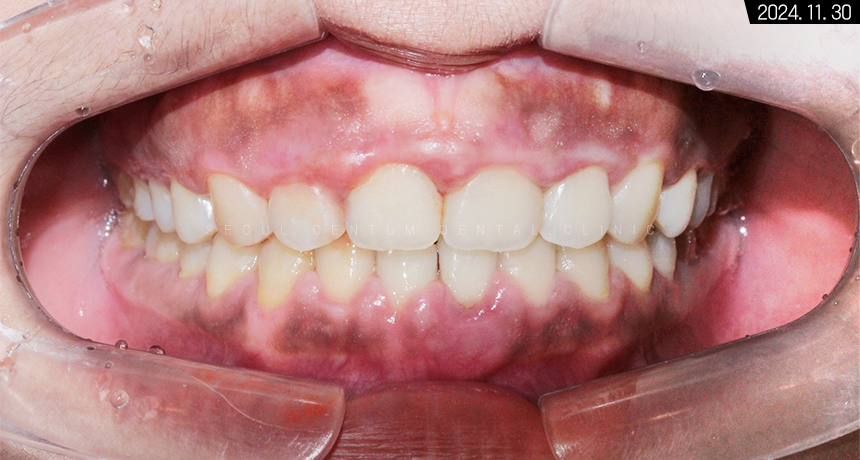

총 1년 5개월 정도의 기간이 지난 후

기존 장치를 모두 떼어내고 나서

유지 장치를 붙여드렸습니다.

치아 교정 후에 확실히 구강 구조가 가지런해졌으며

각도, 전돌 등 정상 범주를 벗어난 부분까지

바르게 만들어져서 훨씬 보기 좋은 모습입니다.

치아 교정을 바르게 마쳐서 그런지

구강을 상하측에서 봤을 때도

이전보다 가지런해진 치열이 보입니다.

중절치 중심선도 일치하고

앞니끼리 톱니바퀴처럼 견고하게 맞물려있고요.

이처럼 구치부부터 전치부까지

어느 하나 비틀어진 곳 없이

바르게 맞물리게 되었습니다.